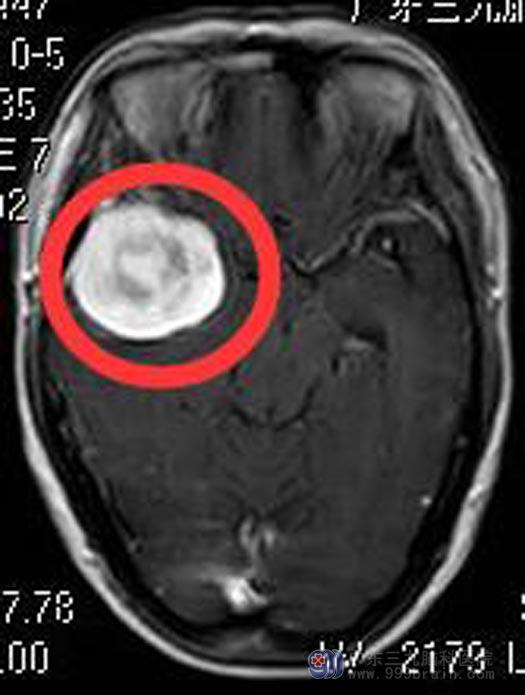

4. 头颅MR检查提示:右侧颞部占位性病变,大小约43mm×36mm×49mm,考虑脑膜瘤可能性大,待排血管周细胞瘤可能。

5. 头颅CTA检查提示:右侧中颅窝底占位性病变,血供丰富,内可见血管分布,邻近右侧大脑中动脉明显受压移位,部分被包绕。

6. 诊断:右侧颞部占位。

7. 手术方式:右侧颞部脑膜瘤切除术。